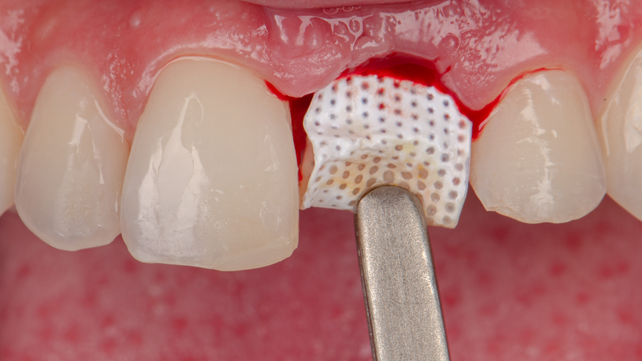

Com o objetivo de preservar o volume ósseo e a morfologia gengival, foi realizada uma regeneração óssea guiada (ROG) com o Extra Graft XG-13 aplicado na região vestibular para preenchimento do GAP entre o implante e a parede óssea. Na sequência, foi colocada uma membrana Cytoplast, em PTFE de alta densidade, adaptada sob o tecido gengival e estabilizada por sutura com nylon azul, promovendo selamento do sítio cirúrgico.

Já a membrana Cytoplast, confeccionada em PTFE de alta densidade (d-PTFE), reúne propriedades que a tornam uma aliada estratégica em procedimentos regenerativos onde o fechamento primário não é possível ou desejado. Seus poros ultrafinos (< 0,3 μm) impedem a penetração bacteriana mesmo quando a membrana está exposta à cavidade oral, proporcionando segurança durante o processo de cicatrização. Além disso, sua superfície texturizada Regentex, com microssulcos hexagonais, favorece a adesão dos tecidos periféricos e bloqueia a migração epitelial sobre o leito enxertado. Isso garante um selamento hermético e previsível do alvéolo, permitindo que a regeneração óssea ocorra sem interferência de tecidos moles. A facilidade de remoção ambulatorial da membrana também elimina a necessidade de nova cirurgia, otimizando o conforto do paciente e a eficiência clínica.